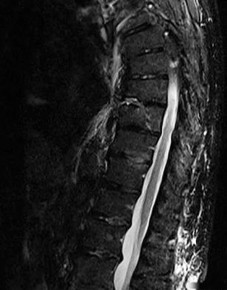

A 60-year-old male with poorly controlled diabetes mellitus presents with severe back pain, fever, and progressive bilateral lower extremity weakness over the past 24 hours. An urgent MRI confirms an anterior epidural abscess at L2-L3.

Blood cultures are drawn. What is the next best step in management?